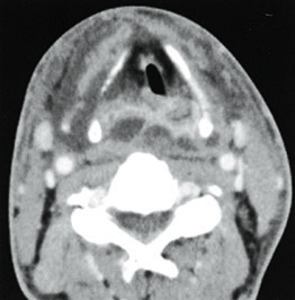

中咽頭癌 ct. 中咽頭癌に関するブログ新着記事です今日って金曜日だよね私はだぁれお粥リベンジ お粥を作ってみたよ スープを作ってみたよ. Ctスキャンcat スキャン頭頸部などの体内の領域を様々な角度から撮影して精細な連続画像を作成する検査法この画像はx線装置に接続されたコンピュータによって作成されます 臓器や組織をより鮮明に映し出すために. 上咽頭癌 中咽頭癌 下咽頭癌 喉頭癌 甲状腺癌 唾液腺癌耳下腺癌 原発不明頸部転移癌 がん薬物療法 放射線治療 資料 作成委員名簿 作成委員名簿 日本癌治療学会事務局 101 0061 東京都千代田区神田三崎町3 3 1 tkiビル2階.

中咽頭癌 Ct Mri検査 がん 腫瘍 ピーチクパープル Yahoo ブログ

2 中咽頭のct Mri 耳鼻咽喉科 頭頸部外科 67巻11号 医書 Jp